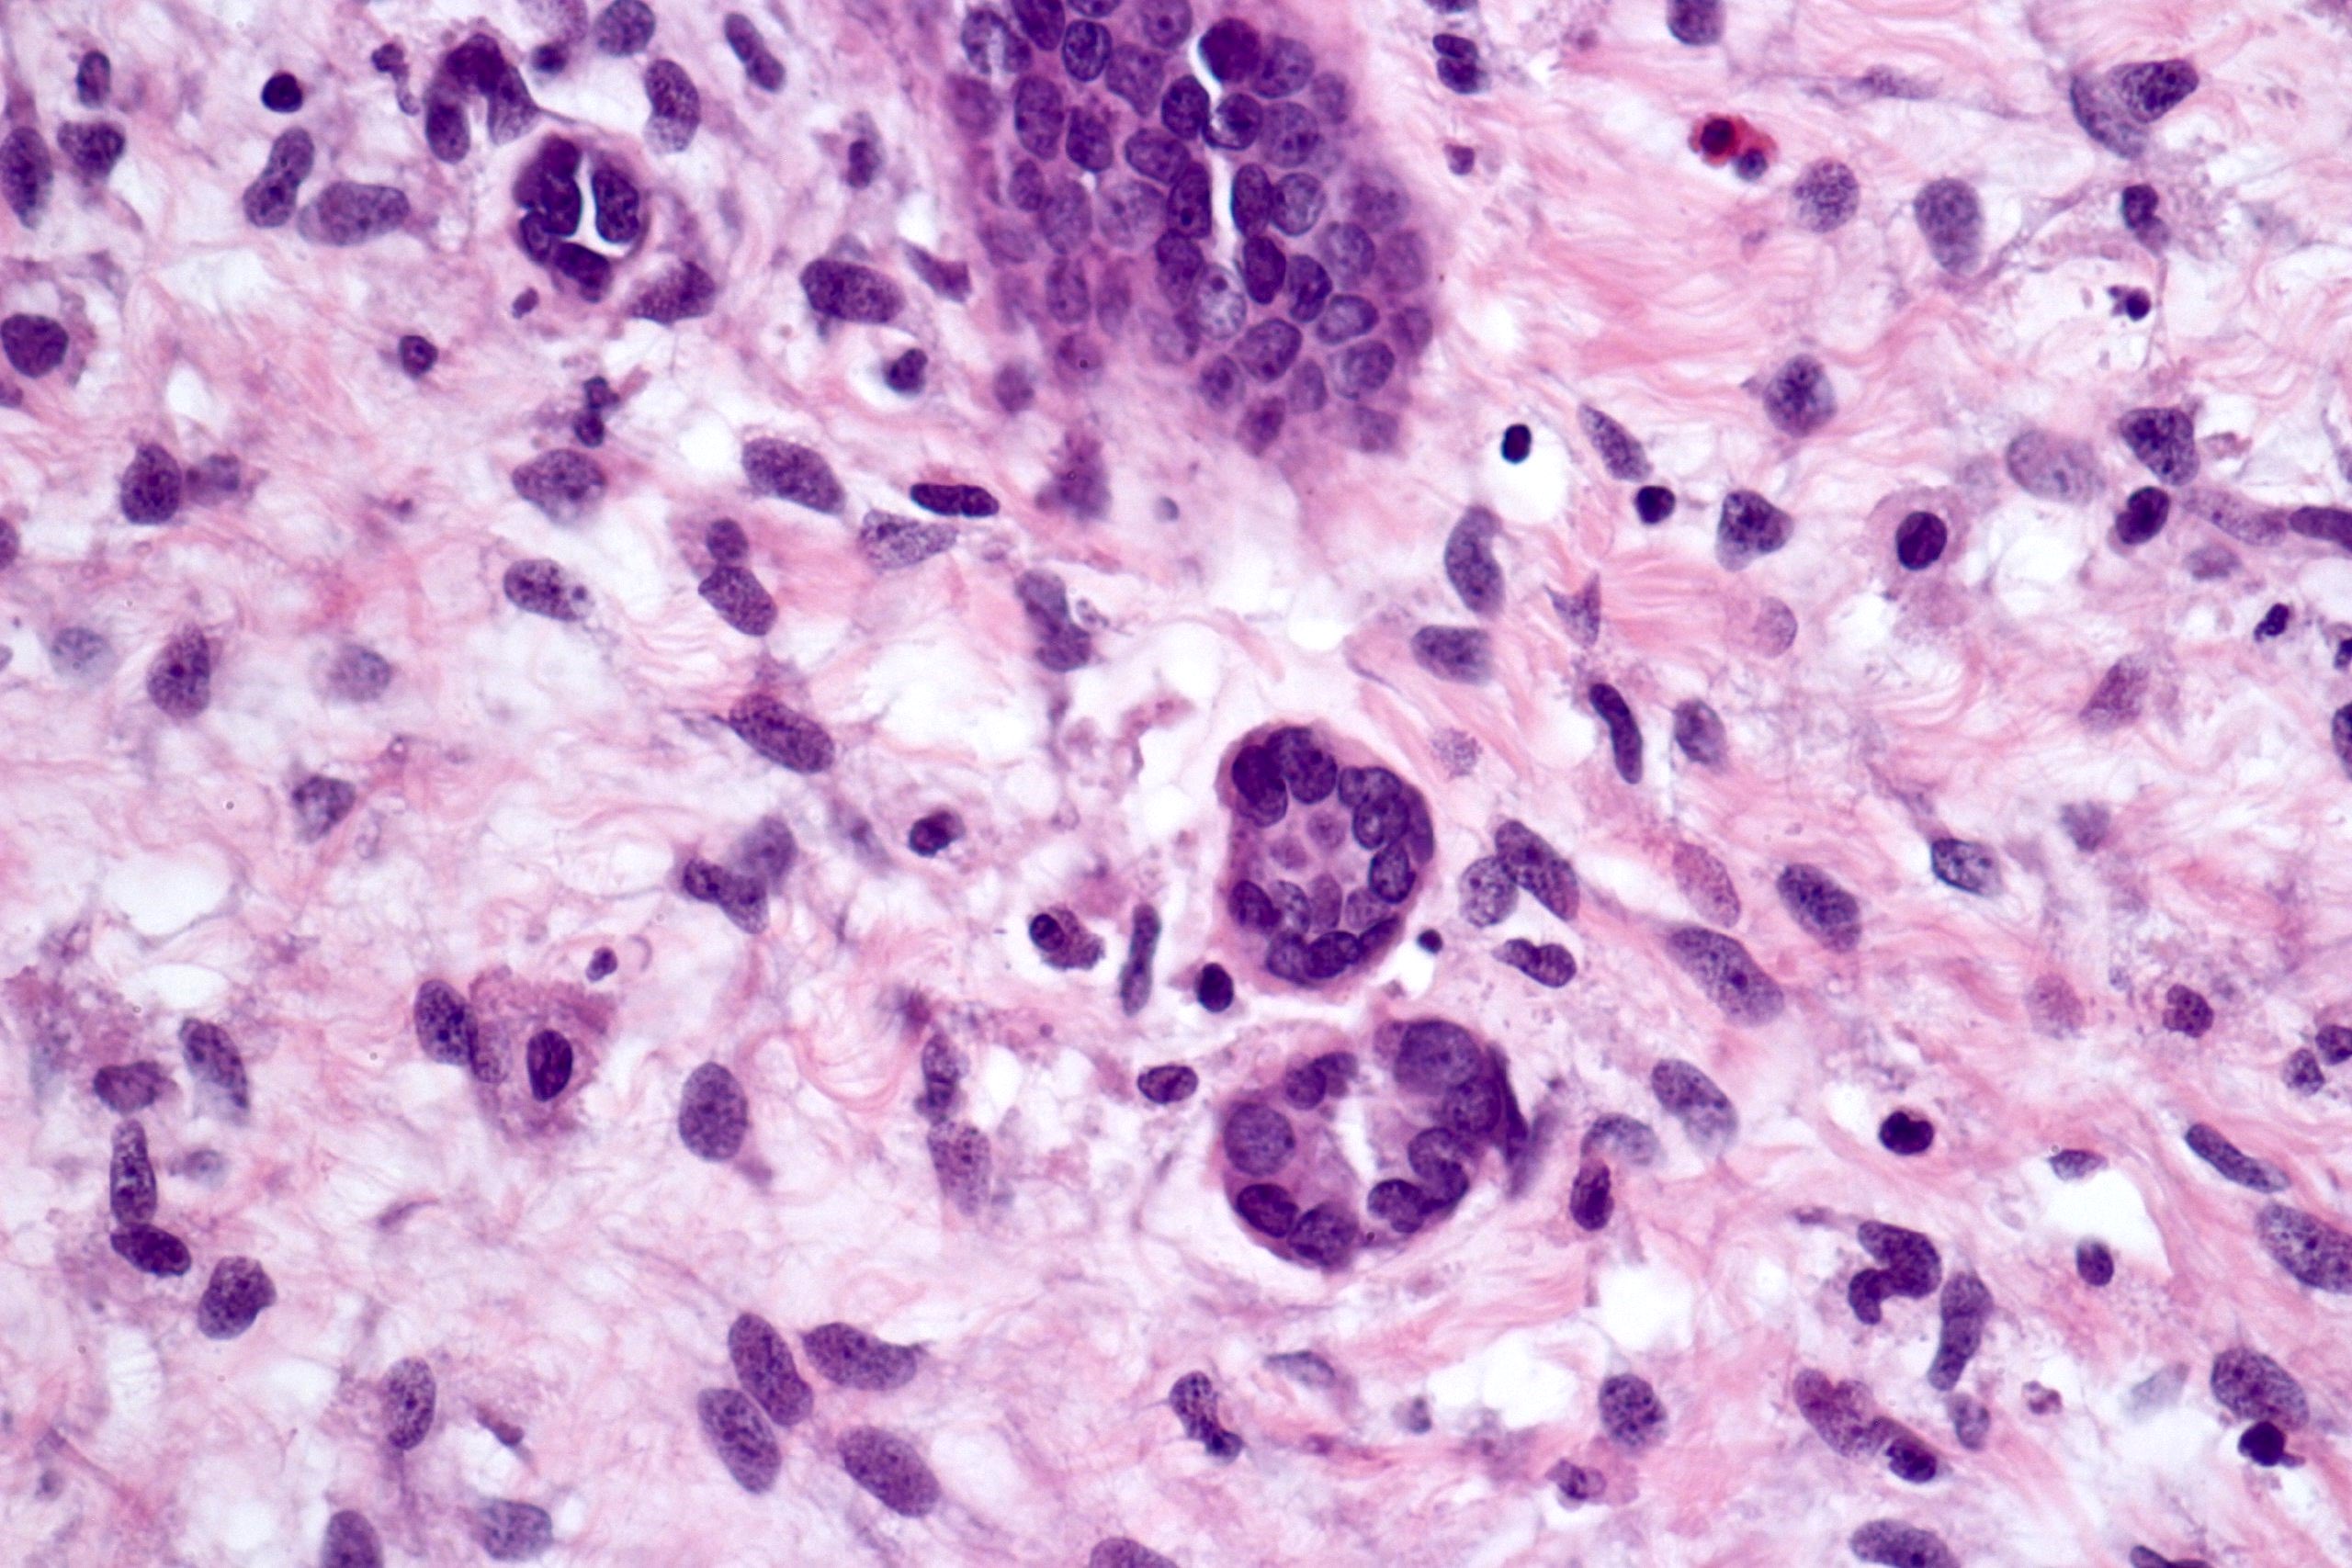

Microscopic (histologic) description

- Cysts lined with flat / cuboidal / hobnail cells (or are denuded)

- Epithelial elements consist mainly of mature and immature / abortive tubules and small papillae resembling immature glomeruli

- Key histological findings of the variably cellular septa include

- Nephroblastomatous epithelial elements

- Islands of undifferentiated blastema and differentiated mesenchymal elements (skeletal muscle and less often cartilage and fat) (J Urol 2010;183:1585)

- Focally, the septal elements may protrude into the cystic spaces in microscopic papillary folds

Microscopic (histologic) images

Contributed by Americo Brilhante, M.D. and Daniel Athanazio, M.D., Ph.D.